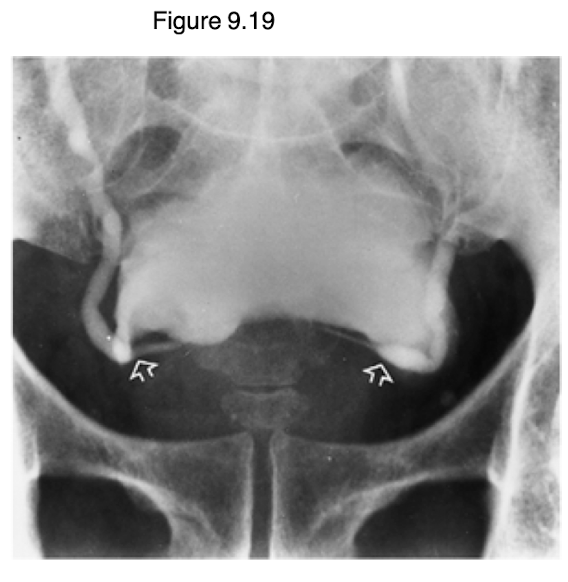

What is vesicoureteral reflux and how is it diagnosed?

Vesicoureteral reflux (VUR) is a condition where urine flows backward from the bladder into the ureters and kidneys, often due to a malfunctioning valve at the ureter-bladder junction.

Juse Cystogram/voiding cystourethrogram